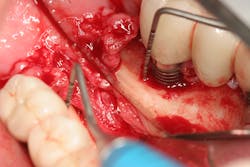

The expense and technical difficulty of removing an implant, rebuilding the defect, and replacing the failed dental implant with a new one can often be challenging. In addition, regenerative treatments for dental implant repair can be both costly and unpredictable if not done correctly (figures 1–3). Long-term maintenance and clinical oversight of peri-implant disease remains the most cost-effective and successful preventive measure for treating this disease.8 If this AI technology helps to determine the failure risk for the patient after surgical repair of the diseased dental implant, explantation with the replacement of a new implant or fixed/removable prosthesis may offer a better treatment alternative.